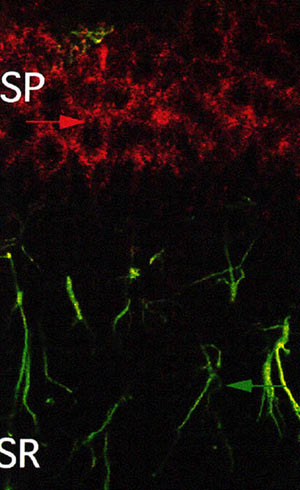

| 砂ネズミのCA1領域におけるSTEPとGFAP抗体の2重免疫染色 |